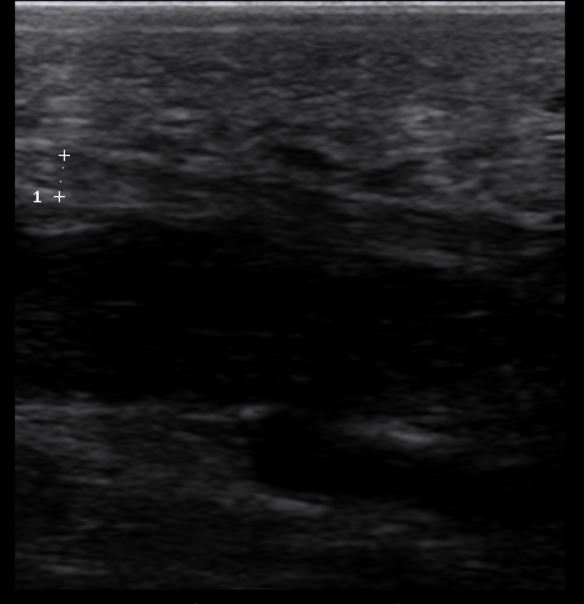

Une échographiest réalisée chez cette patiente montrant : une fasciopathie plantaire ce qui correspond à  une lésion du fascia plantaire induisant un épaississement dégénératif de celui-ci :

Echographie réalisée au centre, démontrant un épaississement du fascia plantaire ou aponévrose plantaire